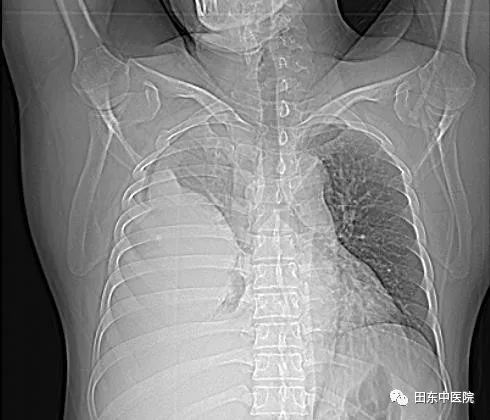

中午12点,一位体型肥胖病人走进了医生办公室,刚好交班结束的我接待了他,他自诉已胸痛了10天有余,先前因腰痛一直在院外治疗,没有好转遂到我院进行进一步的检查。详细了解完其病史后,我为其完善了体格检查:右侧胸胁部疼痛,呈持续性胀痛,有胸闷、呼吸困难,发热畏寒。查体见双侧呼吸运动不对称,两侧触觉语颤不对称,右肺叩诊浊音,右肺呼吸音消失。结合先前他在门诊做过的B超及后续补充的胸部CT结果,发现病人右侧胸腔有大量积液,为了解积液性质及缓解积液对肺脏的压迫,遂给病人行胸腔穿刺置管术,把胸腔里的积液引流出来。过程很顺利,术中抽出了约5000ml伴有腐臭气味的咖啡色脓液,术后病人的疼痛症状得到了极大的改善。

术前